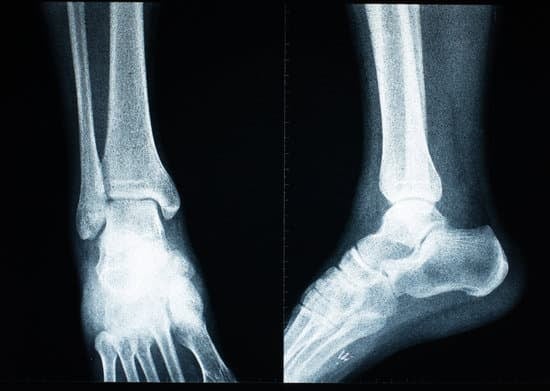

족관절 인공관절 치환술 (Total Ankle Replacement)

족관절 인공관절 치환술은 심하게 손상된 발목 관절을 제거하고,금속과 특수 재질의 인공관절로 대체하여 통증을 줄이고 움직임을 회복하는 수술입니다.

발목뼈(경골)와 거골(Talus)에 각각 금속 인공관절을 삽입합니다.

정기적인 관절 촬영 및 검진으로 인공관절 상태를 확인합니다.

정기적인 엑스레이와 진찰이 중요합니다.